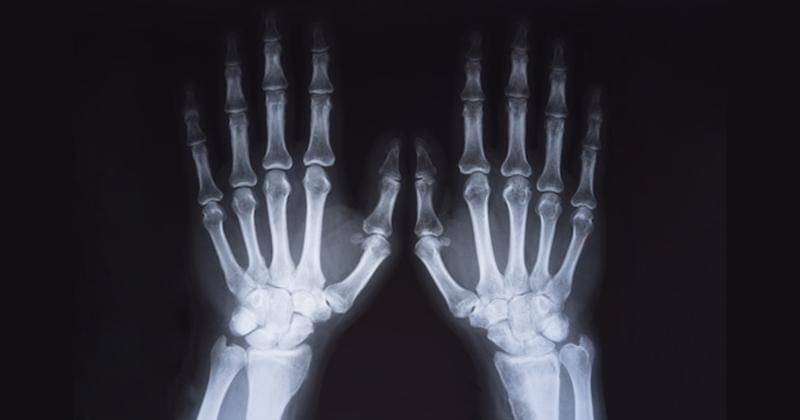

4. Tulang bayi mungil dan stunting juga memiliki perbedaan karena perbedaan asupan nutrisi

Terakhir, Mama bisa melihat perbedaannya melalui perbedaan pertumbuhan tulang pada bone age si Kecil. Untuk anak yang mungil dari sananya akan memiliki bone age sesuai usia.

Sedangkan anak dengan stunting, berhubung terjadi kekurangan nutrisi dalam jangka waktu yang lama maka pertumbuhan tulangnya juga akan terpengaruh. Kurang nutrisi artinya si Kecil kekurangan bahan baku untuk tumbuh.

Sehingga, usia tulang anak yang stunting seringkali di bawah usia seharusnya. Jadi, jangan ragu untuk melakukan pemeriksaan bone age untuk mengetahui pertumbuhan tulang si Kecil. Perlu diingat bahwa pertumbuhan tulang dan tinggi badan bayi sendiri bisa dipengaruhi oleh nutrisi, genetik, hormon, penyakit, dan lainnya.